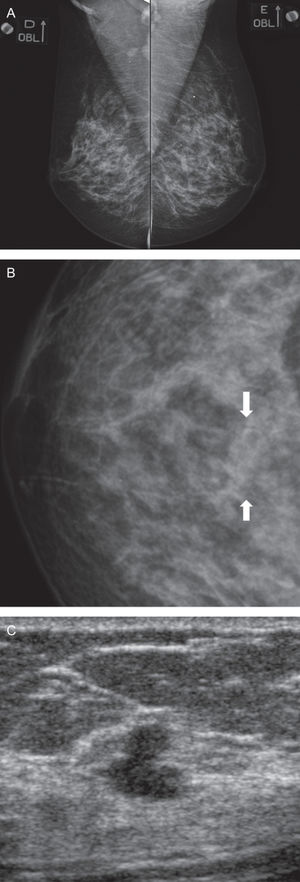

Regarding the 35 patients with Bi-RADS category 4, which was determined by ultrasonography, 25 out of 35 (71.4%) patients had benign findings after the tissue was sampled. However, cancer was found in 10 patients (28.6%) from this group: 5 with Invasive Ductal Carcinoma (Figure 1 -A,B,C), 2 with Ductal Carcinoma in situ, 1 with Invasive Lobular Carcinoma (Figure 2-A,B,C), 1 with a malignant Phyllodes tumor, and 1 with an undifferentiated carcinoma according to immunohistochemistry that was probably associated with the uterine cervix. Mass lesions were predominant in our study. Round or oval lesions, either with circumscribed or indistinct margins, represented 62.5% of the total lesions. Over the follow-up period of at least two years, no lesions that were defined as benign by US were revealed to be malignant.

A-Oblique view of both breasts. A focal asymmetry is seen in the left upper quadrant (arrow). B. Magnified craniocaudal view showed an irregular mass lesion and indistinct margins (arrow). C. US revealed an irregular, hypoechoic mass with indistinct margins (arrow). Core biopsy revealed a Ductal Invasive Carcinoma.